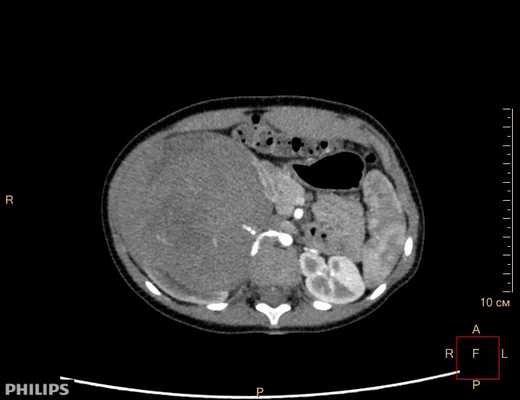

Компьютерная томография брюшной полости и забрюшинного пространства

Компьютерная томография более детально дает информацию об анатомическом отношении опухоли к окружающим тканям и органам, позволяет оценить структуру опухоли (рис. 5).

Рис. 5. КТ нейрогенного образования забрюшинного пространства справа